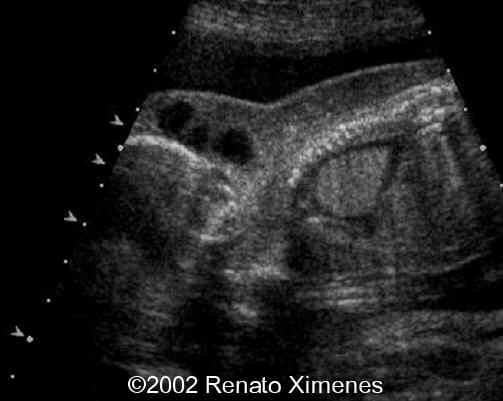

The cystic hygroma extends down the back of the fetus and pleural effusions are visible:

case0072-3

case0072-4

case0072-5